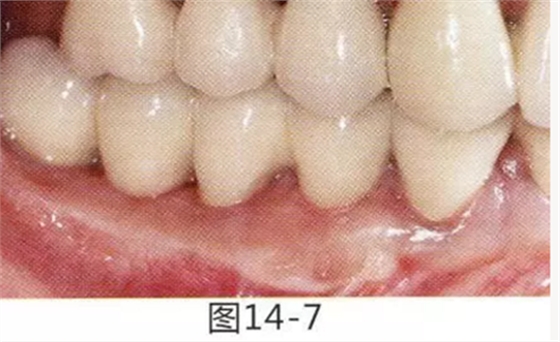

有3~4mm牙周袋并且沒有附著齦的存在,系帶也在牙頸部附近位置的病例。通過FGG(游離齦移植)獲得附著齦同時(shí)切除系帶后,即使經(jīng)過了很長(zhǎng)時(shí)間,牙齦邊緣依然保持安定的狀態(tài)。

圖16-1 右3,4牙周袋探診值為3~4mm,基本沒有附著齦。右下3部位的系帶也附著在牙頸部附近,由于清潔困難而引發(fā)了炎癥。

圖16-2 由于磨牙部缺失,為了能夠進(jìn)行固定修復(fù)而在右下6位置植入種植體,制作右下3,4,5,6固定橋冠。為了增加基牙右下3,4周圍的附著齦,在實(shí)施FGG同時(shí)去除系帶。

圖16-3 獲得了足夠附著齦,可以抵抗刷牙等外部刺激。

圖16-4 獲得充分附著齦,易清潔的狀態(tài)。修復(fù)體之間的鼓形間隙大小均一也使清潔性得到提升。